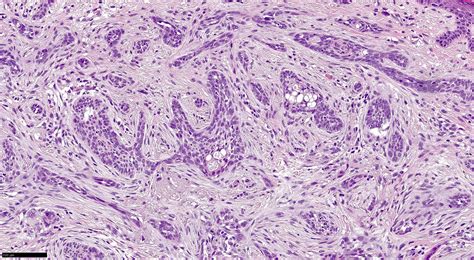

The gold standard for diagnosis is a skin biopsy. During this procedure, a doctor will numb the area and remove a small portion of the lesion to be examined under a microscope by a pathologist. This determines not only the type of cancer but also the depth and aggressiveness of the cells.